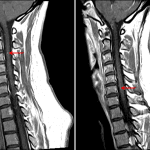

- Multiple T2/STIR hyperintense, short segment lesions in the cervical spinal cord including a midline dorsal lesion at the level of C1, a left lateral lesion at the level of C2-C3, a left dorsal lesion at the level of C3, a right lateral lesion at the level of C5-C6, a left lateral lesion at the level of C6, and a right ventrolateral lesion at the level of C7-T1

- Associated focal intramedullary enhancement on the left at C2-C3 and on the right at C6

- Normal cord contour and volume

- Multiple sclerosis

Multiple T2/STIR hyperintense, short segment lesions in the cervical spinal cord including a midline dorsal lesion at the level of C1, a left lateral lesion at the level of C2-C3, a left dorsal lesion at the level of C3, a right lateral lesion at the level of C5-C6, a left lateral lesion at the level of C6, and a right ventrolateral lesion at the level of C7-T1. This appearance is most consistent with a demyelinating process, particularly multiple sclerosis. Enhancement associated with lesions on the left at C2-C3 and on the right at C6 suggests active demyelination. Recommend brain MRI with and without contrast to assess for intracranial disease.